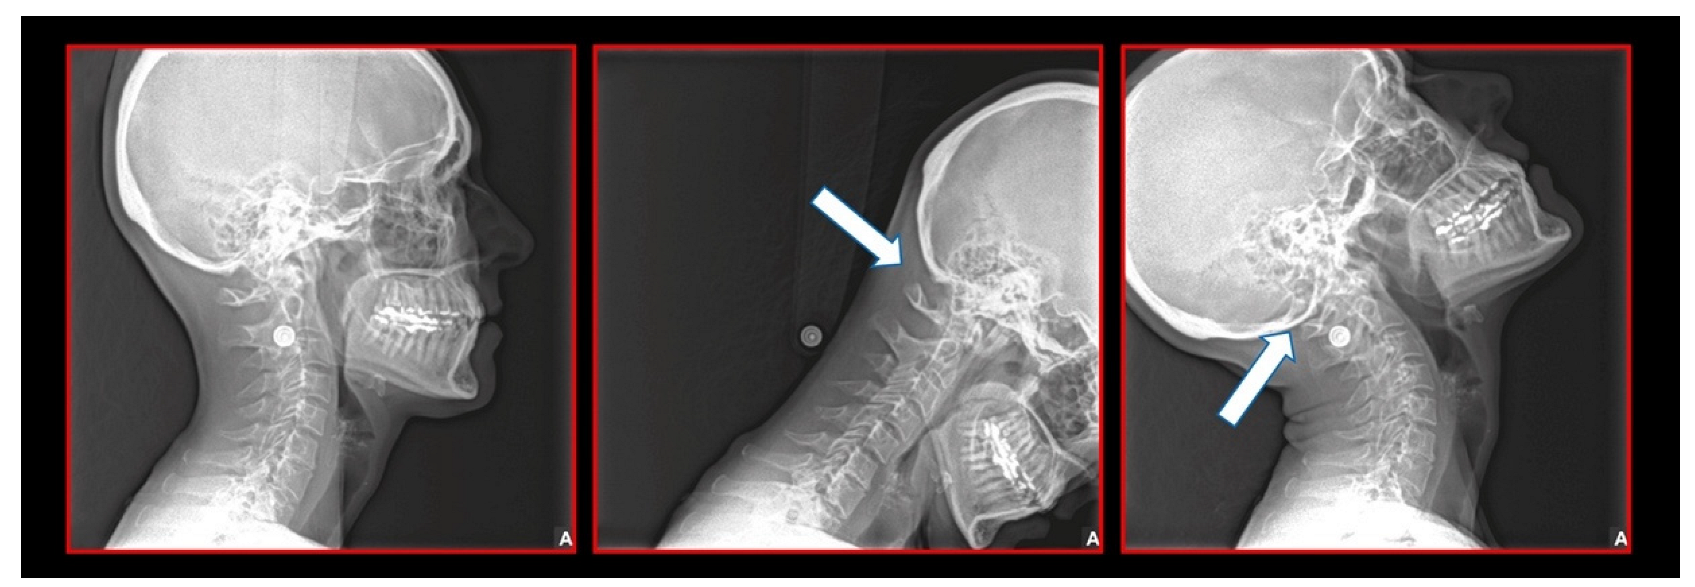

- Rocabado, M.; Gutierrez, R.; Gutierrez, M.F.; Gutierrez, M.J. Case report: Anterior open bite correction treatment by dental treatment and physical therapy through craniocervical mandibular and occlusal stabilization. Cranio 2021, 10, 1–6. [Google Scholar] [CrossRef]